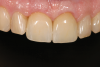

Fig 5. Successful final clinical result of the implant restoration and adjacent teeth.

Figure 5

Fig 11. Restoration at 24-year follow-up.

Figure 11